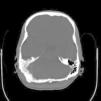

Regarding imaging assessment, abdominal sonography demonstrated ascitis (free fluid in abdomen and pelvic), hypoechoic lesions, calcified lesions and lesions with calcified rim in liver, two similar lesions in pancreas and similar lesions in spleen beside splenomegaly and a 5mm stone and two calcified cyst containing debris in spleen. In chest X-ray (CXR) decreased disk height at T11–T12 level with collapsed T11 vertebral body and paravertebral soft tissue were observed. Abdominal CT showed small sized hypodense lesions in left lobe of liver (Fig. 1), multiple hypodense splenic (Fig. 2) and pancreatic lesions (Fig. 3), left sided pleural effusion, thickening of jejuneal mucosa and edema of bowel wall and ascites (Fig. 4). Vertebral body lesion and paravertebral abscess (Fig. 5), bony calvarial involvement and adjacent extra-axial brain lesion (Fig. 6) are other findings.

Some presentations of extra-pulmonary pnemocystosis are focal low attenuation splenic lesions that becomes progressively calcified; punctuate calcification in the liver, renal cortex and adrenal glands; lymph node calcification, and pleural and peritoneal effusion with subsequent calcification in the surface18 Enlarged heterogeneous spleen with innumerable, low attenuation, hypodense lesions; hepatomegaly; gallbladder wall thickening are some findings reported in extrapulmonary pnemocystosis, as well.15 CXR of our case demonstrated decreased disk height at T11–T12 level with collapsed T11 vertebral body and paravertebral soft tissue. Abdominal CT findings of our case consisted of small sized hypodense lesions in left lobe of liver and multiple hypodense splenic and pancreas lesions, ascitis and left sided pleural effusion, thickening of jejuneal mucosa and edema of bowel wall and ascitis. Vertebral body lesion and paravertebral abscess, bony calvarial involvement and adjacent extra-axial brain lesion are other findings.